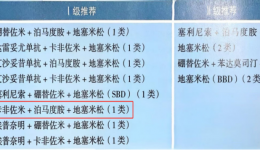

疾病简介:多发性骨髓瘤(MM)是一种克隆浆细胞异常增殖的恶性疾病,是血液系统第2位常见的恶性肿瘤,多发于老年,目前为止仍是不可治愈的血液系统恶性肿瘤,大多数MM患者可能会经历多次复发,而每一次复发后患者产生的耐药性较之前更强,尤其是三...

一、研究背景与现状多发性骨髓瘤(Multiplemyeloma,MM)是第二常见的血液系统恶性肿瘤,蛋白酶体抑制剂如硼替佐米(Bortezomib,BTZ)显著提高了MM的缓解率和存活率,但其对神经组织可产生多方面的副作用,约75%的患者治疗期间发生周围神经病变(P...